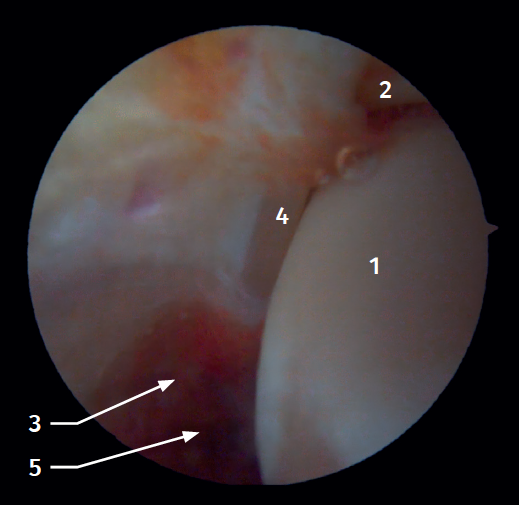

Twenty percent of the ATFL is intra-articular(7). On adopting an anteromedial access of the ankle, directing the arthroscope laterally, we can see the distal fibers of the ATFL with their oblique distribution and their continuation with the anterior talofibular ligament (Figure 2). If we move into the tibiotalar joint, we see the distal tibiofibular joint with the syndesmotic recess occupied by synovial tissue (Figure 3).

Figure 2. Anterolateral arthroscopic view of the right ankle. 1: talar dome; 2: anterior aspect of the tibia; 3: fibula; 4: distal fibers of the anterior tibiofibular ligament; 5: anterior talofibular ligament.

Figure 3. Anterolateral arthroscopic view of a right ankle on entering the tibiotalar zone. 1: talar dome; 2: articular aspect of the tibia; 3: fibula; 4: distal tibiofibular joint; 5: distal fibers of the anterior tibiofibular ligament.